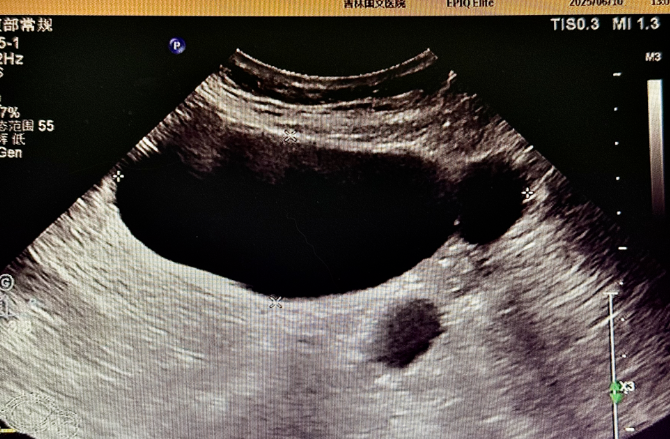

為精準(zhǔn)判斷病情,患者術(shù)前接受了多項(xiàng)影像學(xué)檢查:盆腔 MR 平掃顯示,腹腔內(nèi)存在囊性病灶,周圍伴有管狀影像,為病變定位提供了重要線索,下腹部 CT 進(jìn)一步提示輸卵管擴(kuò)張,腹盆腔內(nèi)可見低密度病灶,與 MR 結(jié)果相互印證,超聲檢查發(fā)現(xiàn)附件區(qū)有管狀無回聲結(jié)構(gòu),經(jīng)超聲科與婦科專家聯(lián)合會(huì)診,綜合分析后診斷為輸卵管積水。多項(xiàng)檢查數(shù)據(jù)的交叉驗(yàn)證,如同為醫(yī)生裝上 “透視眼”,讓隱藏的病灶無所遁形,為后續(xù)手術(shù)方案的制定打下了堅(jiān)實(shí)基礎(chǔ)。